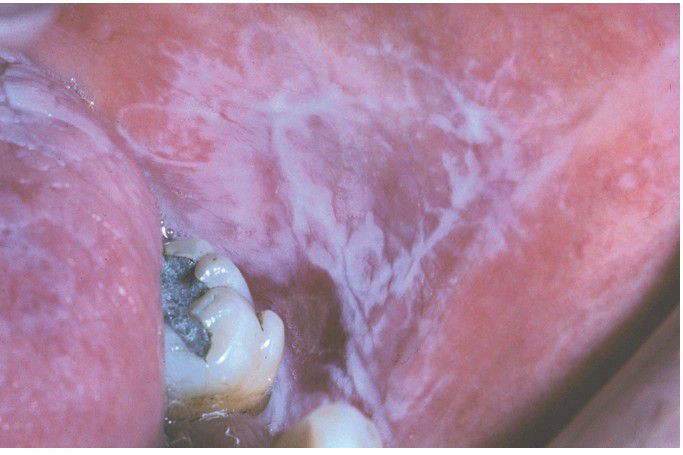

Graft-Versus-Host Disease (GVHD).

Lichenoid lesions of the left buccal mucosa.